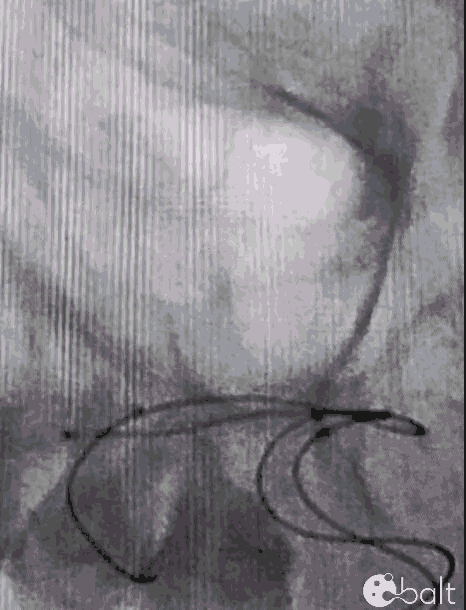

术前影像

颅脑DSA

临床诊断:右侧大脑中动脉M1分叉部宽颈动脉瘤

瘤体大小:5.04*4.56mm。

患者动脉瘤位于大脑中动脉M1分叉部,瘤颈累及M2段上干支和下干支;动脉瘤表面存在多处小的不规则凸起,破裂出血的风险相对较高,且有症状表现,需要手术干预。